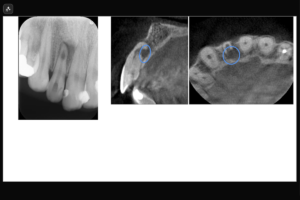

院長が行った根管治療の症例を、レントゲン写真やマイクロスコープ画像とともに解説します。治療のプロセスを透明化し、一つひとつの工程にこだわる専門医院ならではの取り組みをご確認ください。

「抜歯が必要」と診断される歯のすべてが、保存不可能とは限りません。診断が二次元画像や肉眼所見に限られている場合、歯内療法的に重要な情報が見落とされていることもあります。東京は品川駅目の前で歯内療法(根管治療)専門に自由診療で高度な治療を提供している「渡辺歯内デンタルオフィス品川」では、歯科用CTによる三次元評価と拡大視野下での精査を行い、歯の保存可否を専門的に判断します。抜歯は最終手段であり、歯内療法専門医として保存の可能性を最大限検討することが重要だと考えています。

歯の内部という肉眼では確認できない極めて微細な領域を扱う歯内療法において、「何が見えているか」は治療の成否を分ける最も重要な要素です。当院では、再発を最小限に抑え、大切な天然歯を温存するために、世界基準の専門設備を完備した精密な診療体制を整えています。 まず診断においては、歯科用CTを活用し、従来のレントゲンでは把握が困難だった複雑な根管の形態や病巣の広がりを3次元的に解析します。これにより、勘に頼らないデータに基づいた確実な治療計画の立案が可能となります。 実際の処置では、すべての症例において歯科用マイクロスコープ(手術用顕微鏡)を使用します。視野を数十倍に拡大することで、肉眼では見落としがちな微細な亀裂や汚れを正確に捉え、精度の高いアプローチを実現します。当院では世界最高水準を謳う先端歯科診療センターと同等あるいはそれ以上の設備を目指しています。